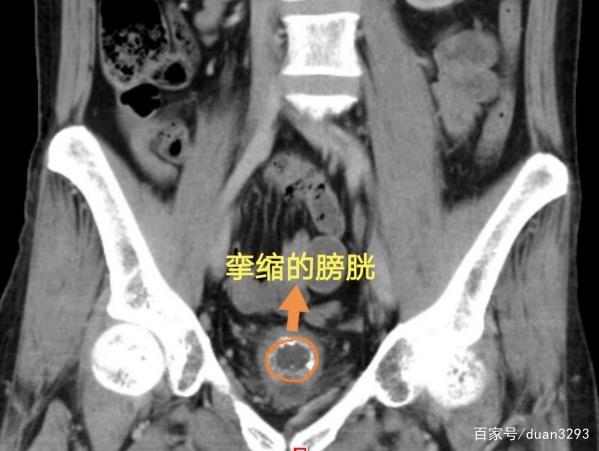

赵先生两年前检查发现患有结核性脑膜炎、肺结核、泌尿系结核,严重结核感染导致左肾积水,左肾坏死。经过一年半规律的抗结核药物治疗,2019年8月在泌尿四科接受了左肾、左侧输尿管切除术,术后尿频有所好转,但过了一段时间,尿频再次严重起来,才又到医院就诊。经过检查,赵先生的膀胱竟然只剩鸡蛋大小,正常人的膀胱容量是300ml-500ml,他的容量只有常人的1/10,医学上称为膀胱挛缩,不仅挛缩,膀胱内还有结石,去年12月接受了膀胱取石、膀胱水扩张术。症状有所改善,术后三个月,因为治疗效果好,赵先生再次来医院做膀胱扩张。

这一次,赵先生的膀胱出现了“弹性”变差的情况,挛缩的膀胱就像是气球失去了弹性,储尿和排空尿液时无法变大缩小,医生为他实施了经尿道膀胱镜下水扩张术,加透明质酸钠灌注。膀胱容量由狭小的30ml扩张至100m l,术后排尿次数明显减少。由于膀胱纤维化严重,容积会逐渐回缩,后续还需再次扩张,赵先生回家后需书写排尿日记,医生将尽最大努力帮助他提高生活质量。